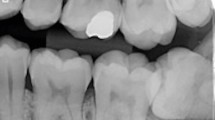

This paper reported a case of fusion between an impacted third molar and a supernumerary tooth, in which a surgical intervention was carried out, with the objective of removing the dental elements. The panoramic radiography was complemented by the Donovan's radiographic technique; but because of the proximity of the dental element to the mandibular ramus, it was not possible to have a final fusion diagnosis. Hence, the Cone‐Beam Computed Tomography—which provides precise three‐dimensional information—was used to determinate the fusion diagnosis and also to help in the surgical planning. In this case report we observed that the periapical, occlusal and panoramic were not able to show details which could only be examined through the cone‐beam computed tomography.